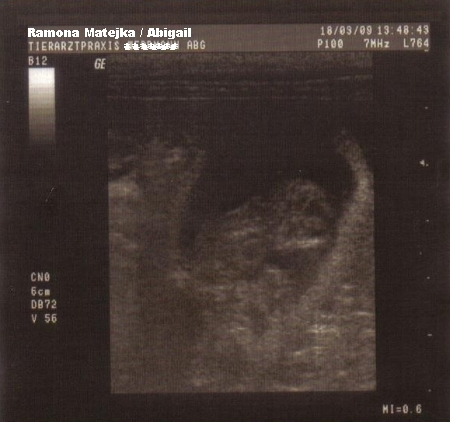

Auf diesem Bild befindet sich der Welpe in bequemer Bauchlage, rechts kann man sehr gut das kleine Köpfchen erkennen. Der Welpe ist 44 Tage alt und bereits

ca. 6 cm groß.